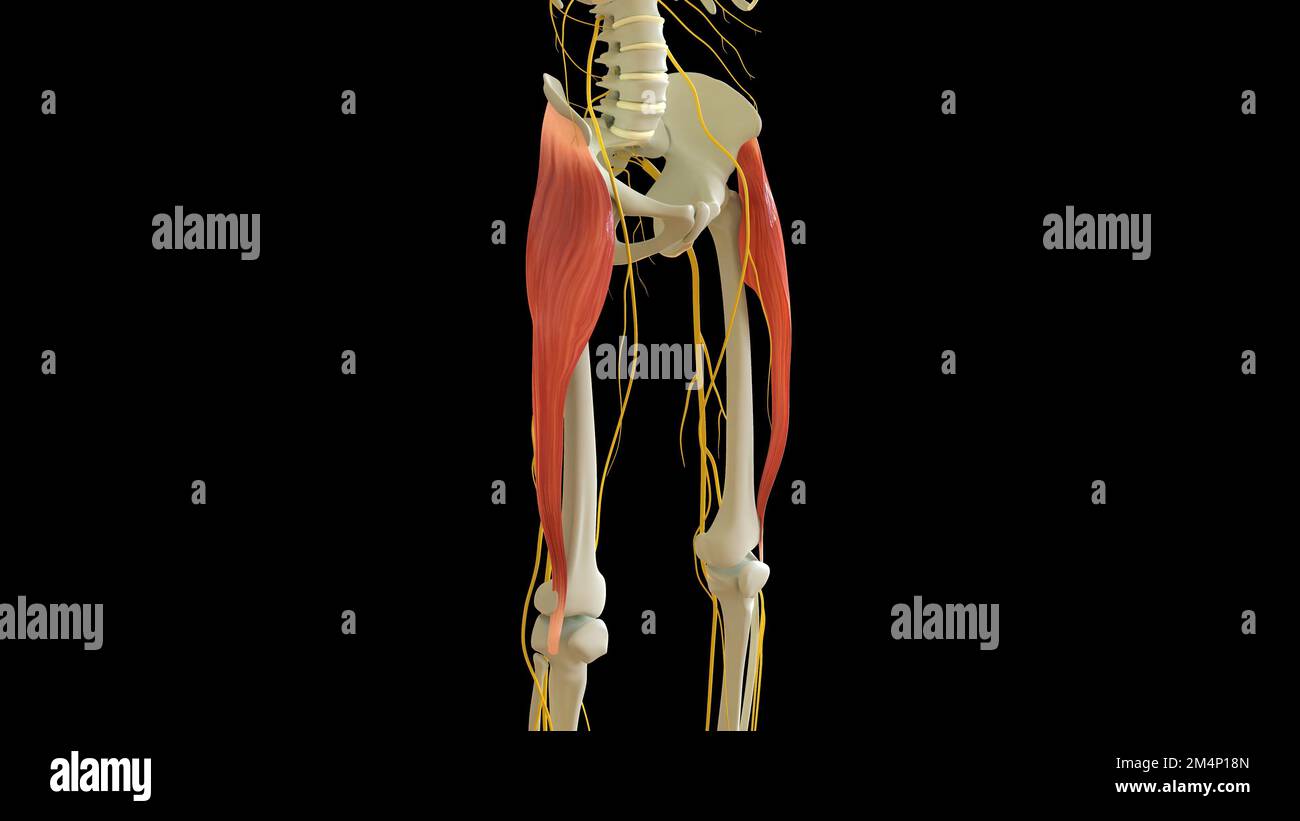

Tensor Fasciae Latae Muscle anatomy for medical concept 3D illustration Stock Photohttps://www.alamy.com/image-license-details/?v=1https://www.alamy.com/tensor-fasciae-latae-muscle-anatomy-for-medical-concept-3d-illustration-image502043269.html

Tensor Fasciae Latae Muscle anatomy for medical concept 3D illustration Stock Photohttps://www.alamy.com/image-license-details/?v=1https://www.alamy.com/tensor-fasciae-latae-muscle-anatomy-for-medical-concept-3d-illustration-image502043269.htmlRF2M4P18N–Tensor Fasciae Latae Muscle anatomy for medical concept 3D illustration